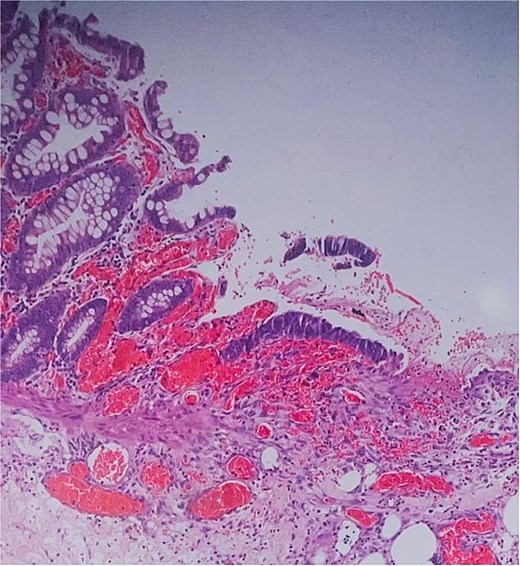

Histological evaluation confirmed acute necrotizing colitis with transmural inflammation and granulation tissue (Figs 4 and 5). Hepatic cyst biopsies revealed benign biliary duct cysts with cystically dilated bile ductules.

Histopathology: surface ulceration with perforation as indicated by fat lobules (arrow).

Histopathology: complete surface ulceration with granulation tissue (H&E, × 40).